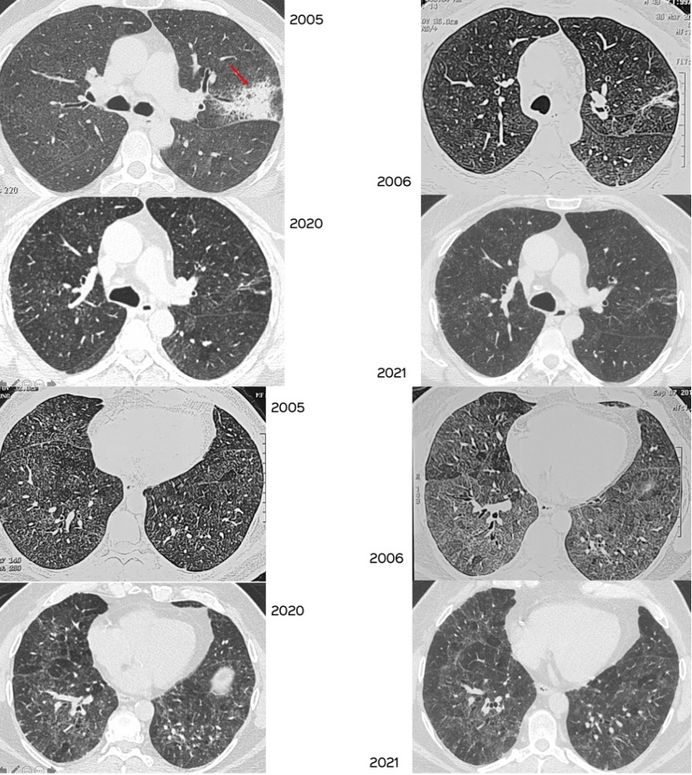

From www.researchgate.net

Chest CT scans shown signs of pneumonia. Download Scientific Diagram Will A Chest Ct Show Pneumonia We can see abnormalities such as pneumonia, lung cancer, emphysema, effusions or fluid around the lungs, and many others. When chest ct shows an obvious alternate diagnosis (e.g. A ct scan of the chest may be done to see finer details within the lungs and detect pneumonia that may be more difficult to. Radiologists will also look for spread of. Will A Chest Ct Show Pneumonia.

From pubs.rsna.org

Radiographic and CT Features of Viral Pneumonia RadioGraphics Will A Chest Ct Show Pneumonia When chest ct shows an obvious alternate diagnosis (e.g. We can see abnormalities such as pneumonia, lung cancer, emphysema, effusions or fluid around the lungs, and many others. But in most cases, you can’t tell simply from the ct scan. Radiologists will also look for spread of your cancer such as enlarged. Bacterial lobar pneumonia or left ventricular failure), the. Will A Chest Ct Show Pneumonia.